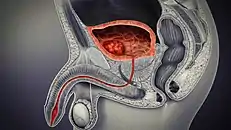

Cancer

Cancer of the bladder is known as bladder cancer. It is usually due to cancer of the urothelium, the cells that line the surface of the bladder. Bladder cancer is more common after the age of 40, and more common in men than women;[30] other risk factors include smoking and exposure to dyes such as aromatic amines and aldehydes.[30] When cancer is present, the most common symptom in an affected person is blood in the urine; a physical medical examination may be otherwise normal, except in late disease.[30] Bladder cancer is most often due to cancer of the cells lining the ureter, called transitional cell carcinoma, although it can more rarely occur as a squamous cell carcinoma if the type of cells lining the urethra have changed due to chronic inflammation, such as due to stones or schistosomiasis.[30]

Investigations performed usually include collecting a sample of urine for an inspection for malignant cells under a microscope, called cytology, as well as medical imaging by a CT urogram or ultrasound.[30] If a concerning lesion is seen, a flexible camera may be inserted into the bladder, called cystoscopy, in order to view the lesion and take a biopsy, and a CT scan will be performed of other body parts (a CT scan of the chest, abdomen and pelvis) to look for additional metastatic lesions.[30]

Treatment depends on the cancer's stage. Cancer present only in the bladder may be removed surgically via cystoscopy; an injection of the chemotherapeutic mitomycin C may be performed at the same time.[30] Cancers that are high grade may be treated with an injection of the BCG vaccine into the bladder wall, and may require surgical removal if it does not resolve.[30] Cancer that is invading through the bladder wall may be managed by complete surgical removal of the bladder (radical cystectomy), with the ureters diverted into a segment of part of ileum connected to a stoma bag on the skin.[30] Prognosis can vary markedly depending on the cancer's stage and grade, with a better prognosis associated with tumours found only in the bladder, that are low grade, that do not invade through the bladder wall, and that is papillary in visual appearance.[30]